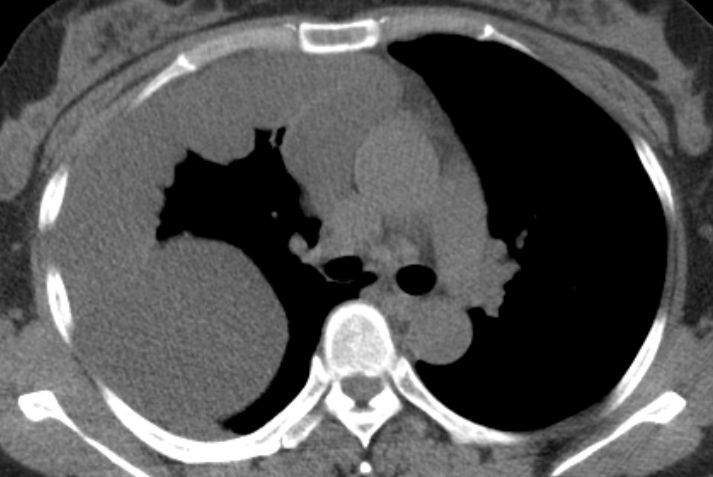

胸膜间皮瘤1例ct影像鉴别